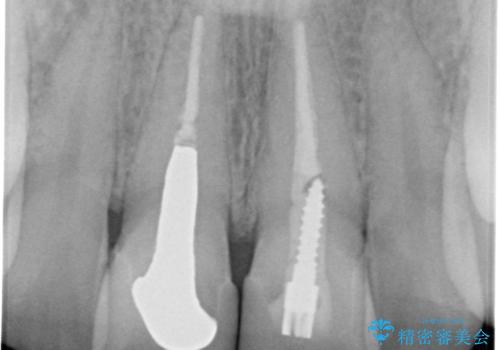

- 前歯のかぶせ物の変色を主訴に来院された患者様です。

根管治療からのやり直しはご希望されませんでした。

今回はe-maxクラウンで修復していきます。